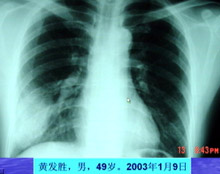

主持人:来看两位广东省中医院被感染了非典型肺炎的患者的情况: 钟医生:现在回想起来我接触了一位叫黄发胜的病人以后的三天就开始发烧,还以为是一般的普通发烧,但是过了三天以后烧还是退不了,这时又出现了胸口疼痛,照了个胸片后发现右下肺有感染,接着就住院了。 黄发胜(广东省第一例非典患者):"当时我的病很重,右下肺呼吸减得很弱,肺部里面有花斑点,有空洞,还有气囊和气囊泡,靠吸氧气维持呼吸,特别到了1月14号,大概住院5天以后就感到呼吸困难,发了病重通知,当时我的感觉是这种病和一般的肺炎不一样,特别难治,人也特别幸苦。"

主持人:王丽(护士)是什么时候感染的? 王丽:我自己也不能明确说出自己的感染潜伏期有多长,但是我有明确的非典病人接触史,因为我在重症病房工作,3月13日我刚下班就发现自己双腿比较软,人有一种往下坠的感觉,开始以为是太疲劳导致的,回到宿舍量体温发现体温是38.4度,这时我赶紧就给科室打电话,然后拍了一个胸片后最终确诊为非典型肺炎。 张敏州:钟医生是我院第一个明确感染非典型肺炎的病人,最开始并不知道是感染了非典型肺炎,和黄丽护士一样开始都有疲乏无力的症状。 林琳:来看看胸片的情况:黄发胜的胸片可以看到一大片的阴影,发生了实变,正常的肺泡是充满空气的,而现在黄发胜的胸片显示没有空气。钟医生的胸片可以看到肺叶有发炎的现象。非典型肺炎的发病与季节有很大的关系,春天是呼吸系统疾病的高发季节。